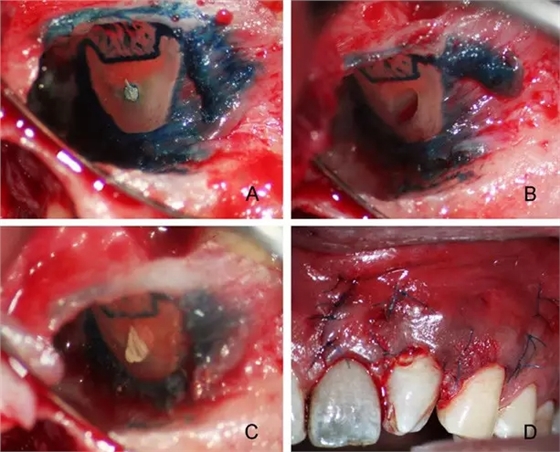

A:根尖切除 B:超聲根尖倒預(yù)備 C:根尖倒充填 D:顯微縫合